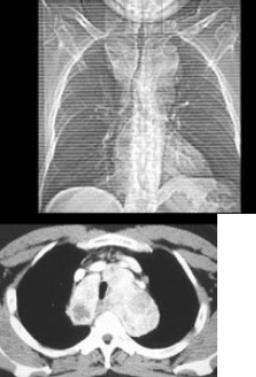

患者男,41岁,体检X线提示纵隔增宽,CT检查如图,最可能的诊断是()。

A、淋巴瘤

B、纵隔畸胎瘤

C、胸腺瘤

D、间皮囊肿

E、胸内甲状腺肿

E